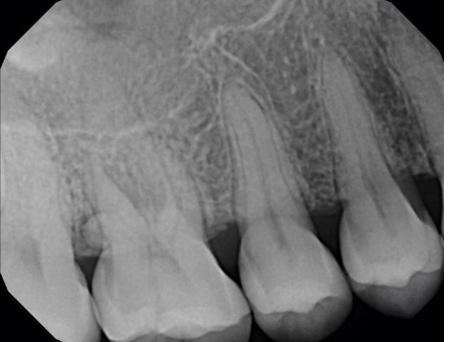

What dental anomaly is seen in this image?

supernumerary tooth

external root resporption

dens in dente

dilaceration

taurodontism

congenitally missing tooth